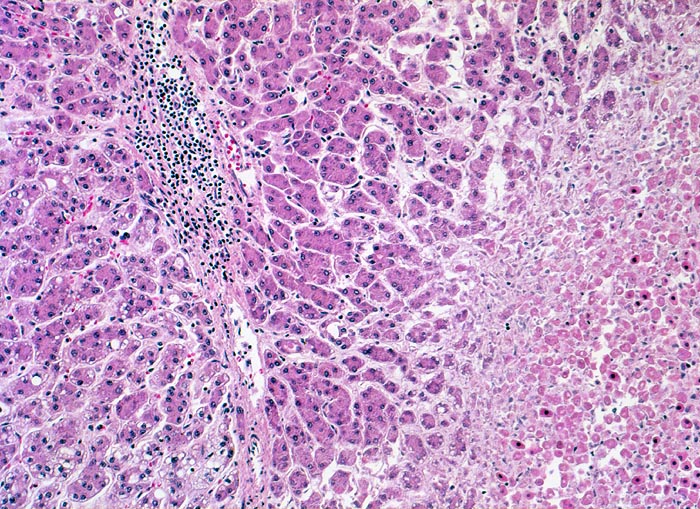

PathoPic – image database / PathoPic ID 4422 - hepatozelluläres Karzinom mit Tumornekrosen

hepatozelluläres Karzinom mit Tumornekrosen

Die Tumortrabekel sind in diesem Tumorabschnitt lediglich zwei Zellen breit. Lediglich die minimalen Zellatypien (verminderte Menge basophiles Zytoplasma, geringe Kernatypien) ermöglichen die Unterscheidung von einem Leberzelladenom. Das Tumorgewebe enthält fibröse entzündlich infiltrierte Septen mit Gefässen. Portalfelder mit Gallengängen fehlen. Das nekrotische Tumorgewebe ist heller gefärbt.

Patient mit bekannter chronischer Hepatitis C. Bei einer sonographischen Kontrolluntersuchung wird ein 1cm grosser Knoten entdeckt. Das Alpha-Fetoprotein im Serum ist nicht erhöht.